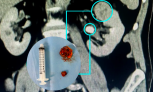

A cirurgia robótica revolucionou o tratamento dos tumores renais. Com visão tridimensional ampliada, movimentos extremamente precisos e maior estabilidade, o cirurgião consegue identificar com clareza os limites do tumor, preservar praticamente 100% do parênquima renal saudável, reduzir o tempo de isquemia (tempo em que o rim fica temporariamente sem fluxo sanguíneo) e garantir segurança oncológica.

Na prática, a tecnologia amplia as possibilidades. O urologista consegue indicar a cirurgia poupadora de néfrons, que é a nefrectomia parcial, em praticamente todos os casos de tumores renais. Isso significa mais preservação, mais função e mais qualidade de vida, no longo prazo.